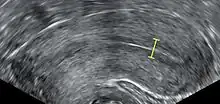

Triple-line endometrium measuring 7mm.

Observation of the endometrium by transvaginal ultrasonography is used when administering fertility medication, such as in in vitro fertilization. At the time of embryo transfer, it is favorable to have an endometrium of a thickness of between 7 and 14 mm with a triple-line configuration,[21] which means that the endometrium contains a hyperechoic (usually displayed as light) line in the middle surrounded by two more hypoechoic (darker) lines. A triple-line endometrium reflects the separation of the basal layer and the functional layer, and is also observed in the periovulatory period secondary to rising estradiol levels, and disappears after ovulation.[22]